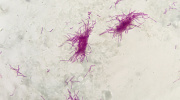

Die Hustenbedeutung ist einfach. Der Körper bemüht sich dadurch, freie Atemwege zu halten, das der Schleim, die Speichel oder ein zufällig eingeatmetes Essen und Trinken verhindern können. Die, die Atemwege bedeckenden Schleimhäute produzieren auf ihrer Oberfläche eine kleine Menge des Schleims. Er verhindert so das Austrocknen der Haut und fängt unangenehmen Staub aus der Umgebung auf. Wenn sich auf der Schleimhaut ein Virus festsetzt, beginnt sie sich durch die Bildung des Schleims zu wehren, den man anschließend hustet. In solchem Fall kann Schleim dick werden und auch das Atmen selbst kann sehr schwierig werden. Man fühlt verstopfte Nase, spricht schlecht und der Hals tut ihm weh.